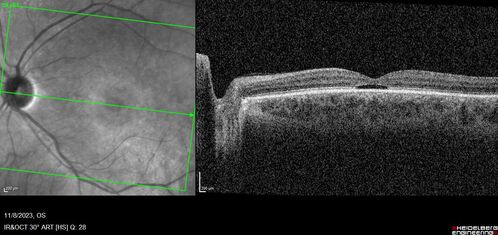

Achromatopsia

28 year old female Good vision since birth started wearing glasses at 2, denies trauma. She does have congenital nystagmus.

VA OD: Dcc20/200-2 PH20/200 NccJ7

VA OS: Dcc20/160 PHNI NccJ7

IOP: TP: OD:15 OS:12